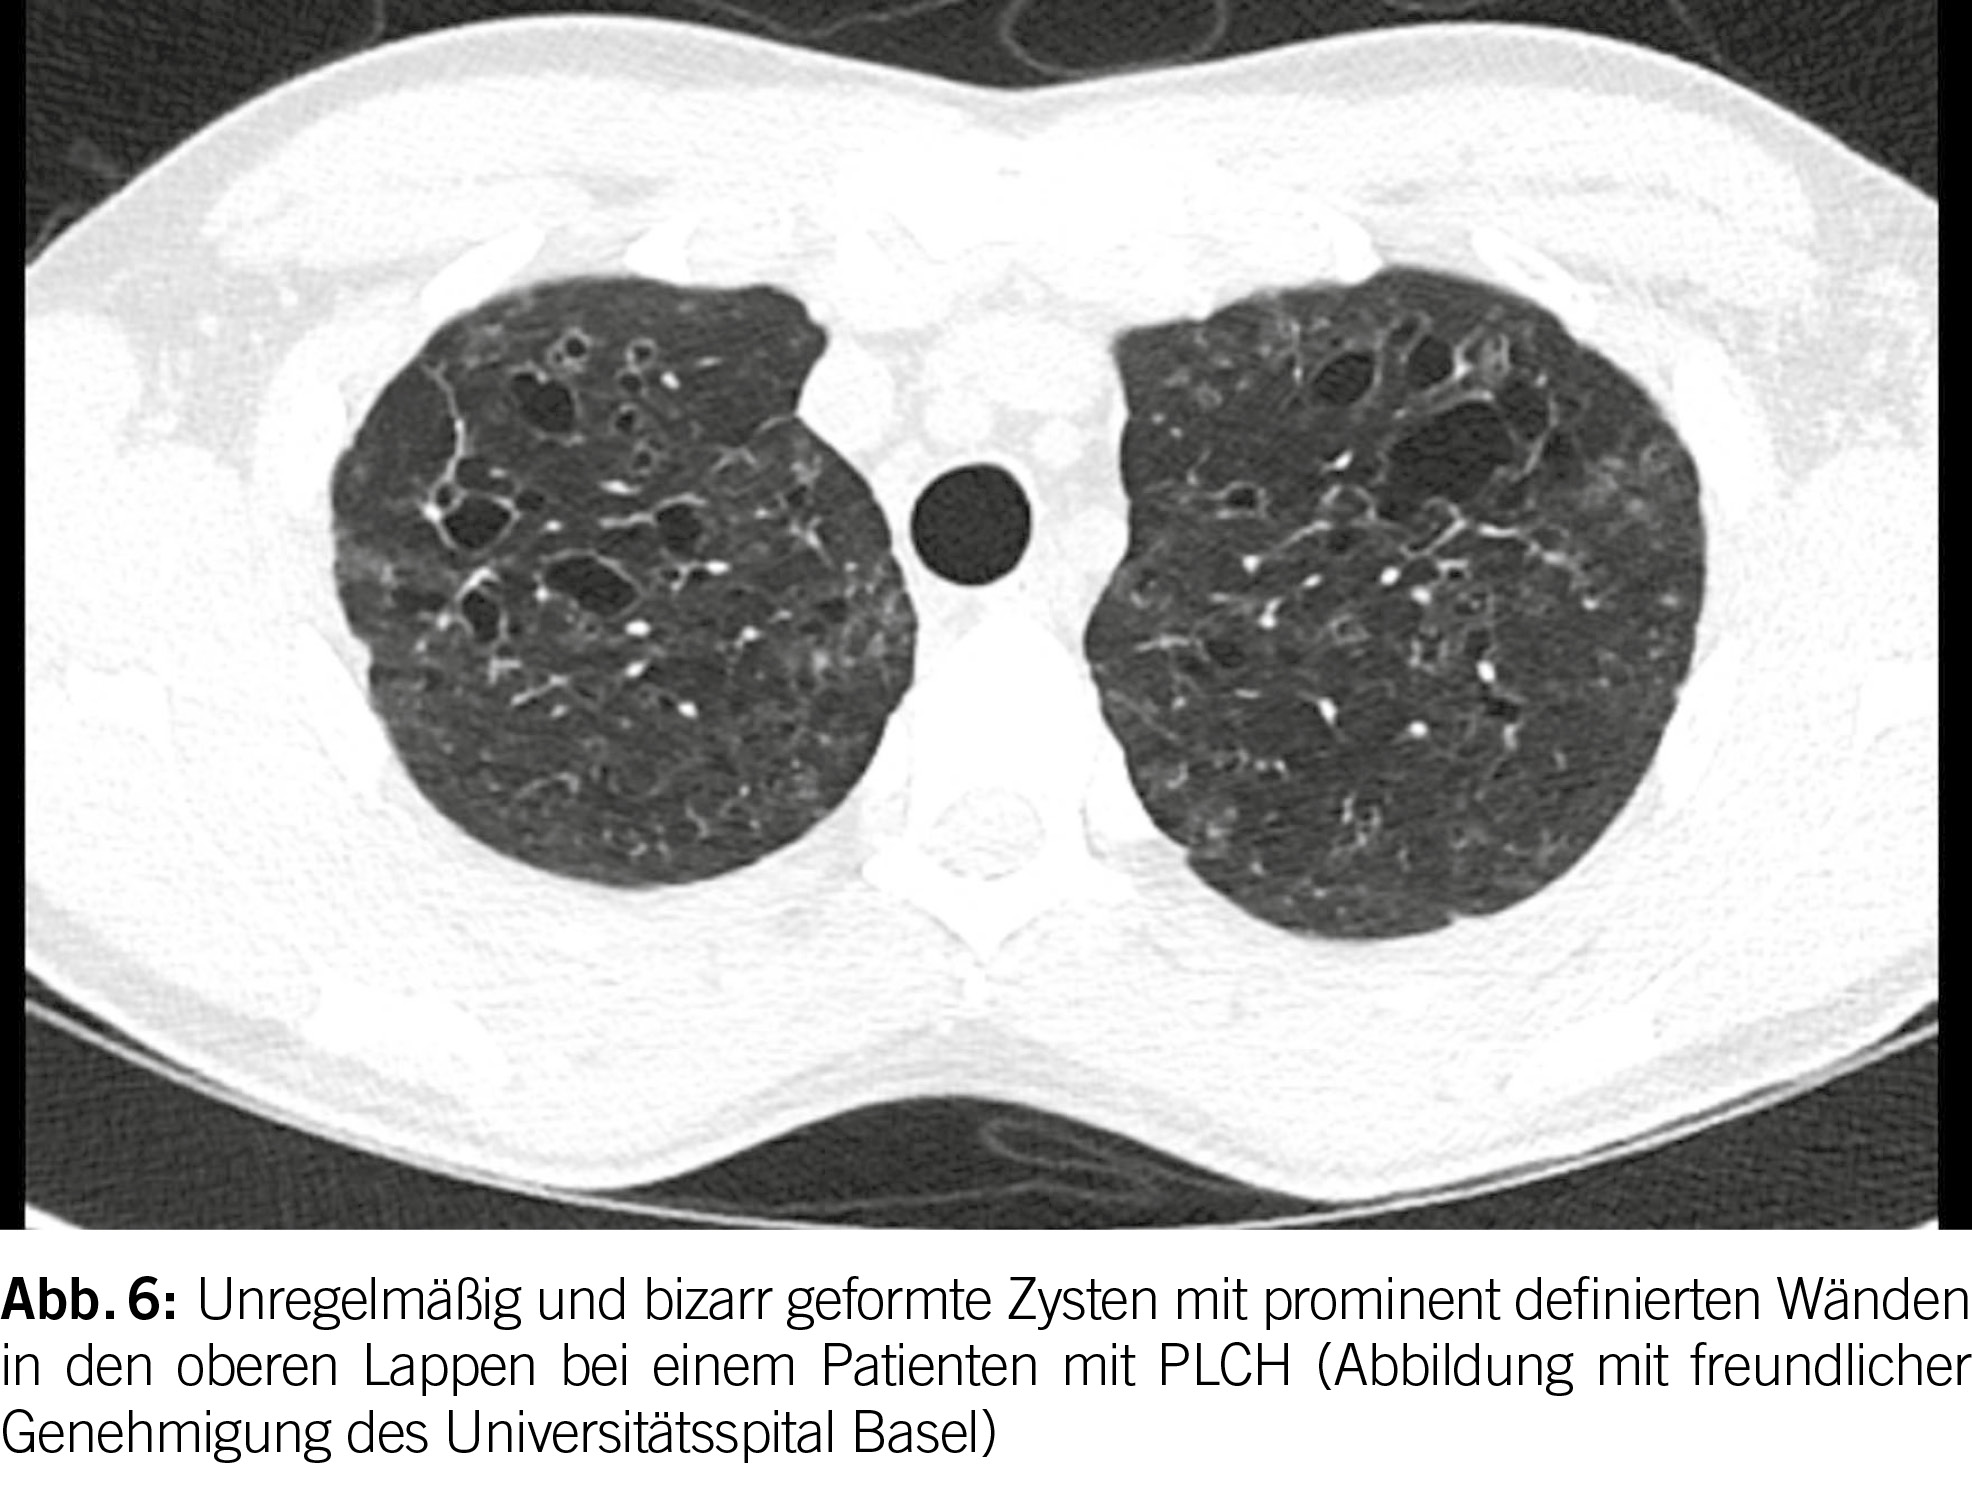

Die hochauflösende Computertomographie (HRCT) spielt eine entscheidende Rolle bei der Evaluation von PLCH. Das charakteristische Merkmal ist das Vorhandensein von diffusen Zysten und Noduli, die sich überwiegend in den mittleren bis superioren Bereichen der Lungen ansammeln, wobei der kostophrenische Winkel nicht befallen ist (20) (Abbildung 6). Die Noduli weisen oft eine schlecht definierte Form auf und messen typischerweise zwischen 2 und 10 mm.